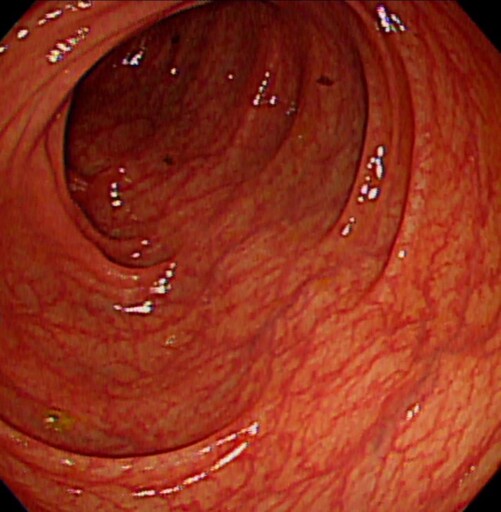

60歲的男性小陳(化名),在30多歲時就確斷為FAP, 做過預防性全大腸切除術,目前都無癌化的狀況,其兒子每幾年都會行大腸鏡檢查,30歲時也發現其大腸內出現數百顆小瘜肉,經醫師建議評估後,也同樣安排預防性全大腸切除術,目前恢復良好。

嘉義基督教醫院大腸直腸科主任朱峻廷醫師表示,FAP是顯性遺傳疾病,只要父母其中一方帶有突變基因,下一代就有50%的機率會遺傳到。根據統計,FAP患者通常在青少年時期就開始出現大腸瘜肉,到了30歲左右,腸道可能布滿上百、上千顆瘜肉,若未治療,90%以上會在中年以前癌化,「只要活得夠久,終其一生幾乎百分之百會演變成大腸癌」。這也是為什麼醫界會不斷強調,一旦家族中有人年輕時就罹患大腸癌或出現大量瘜肉,其他成員必須提高警覺。

另一名40歲的男性小林(化名),在外院行大腸鏡檢查時發現其大腸內出現數百顆大小不一的瘜肉,在等待檢查報告的期間,因腸阻塞被送到嘉基急診,經基因檢測確認罹患了FAP,同時降結腸瘜肉已有癌化跡象並造成腸阻塞;後續進一步檢查又發現小林同時還罹患十二指腸壺腹癌及肝癌,經歷三次手術及多專科團隊的努力,終於將所有的病灶都完整的切除乾淨。